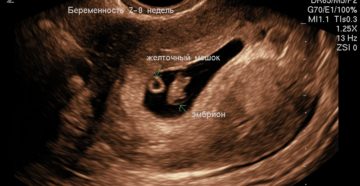

Узи на 7 неделе беременности: фото, размер плода Большинство женщин на определенном этапе своей жизни…

7-я неделя беременности: симптомы и ощущения, УЗИ 7 неделя беременности — срок, на котором полностью…